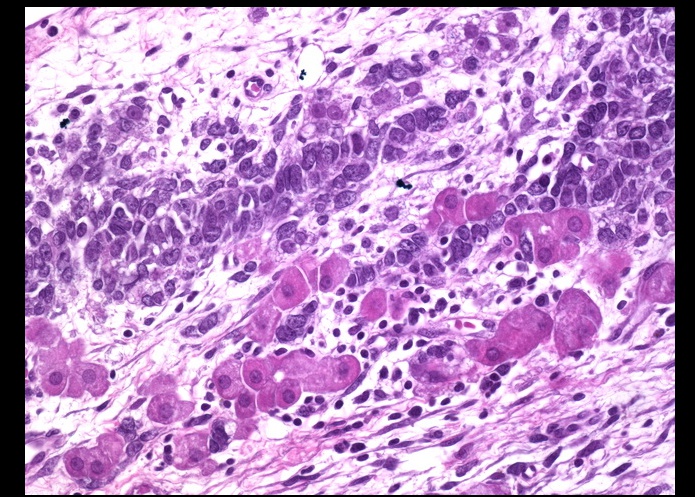

_Histology reveal cells with scanty cytoplasm and angulated, coffee-bean, grooved nuclei. The classic features are Call-Exner bodies., which are granulosa cells arranged in small follicles filled with eosinophilic secretions in the center.

Call-Exner Bodies seen in granulosa cell tumor